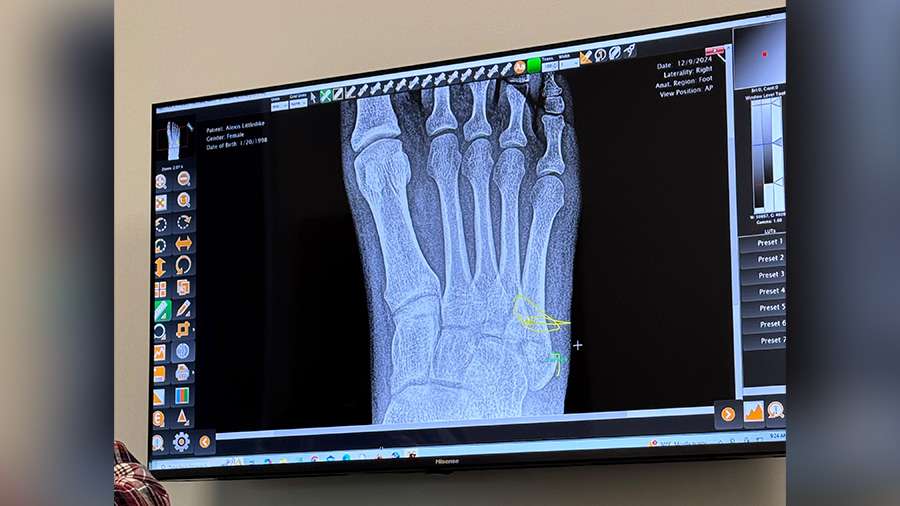

"You don't think something this bad will happen until it does," said Lexie Littledike. While wearing her platform boots one day, Littledike tripped and fell in her garage.

"My foot just kind of did the whole rolling thing. So, I heard a pop," she said. "I went down, and I could immediately see the bone, the big bump popping out to the side."

Littledike had to have surgery for her broken foot. She's now in a boot and on crutches, having to adjust her lifestyle for what she says was a preventable injury.